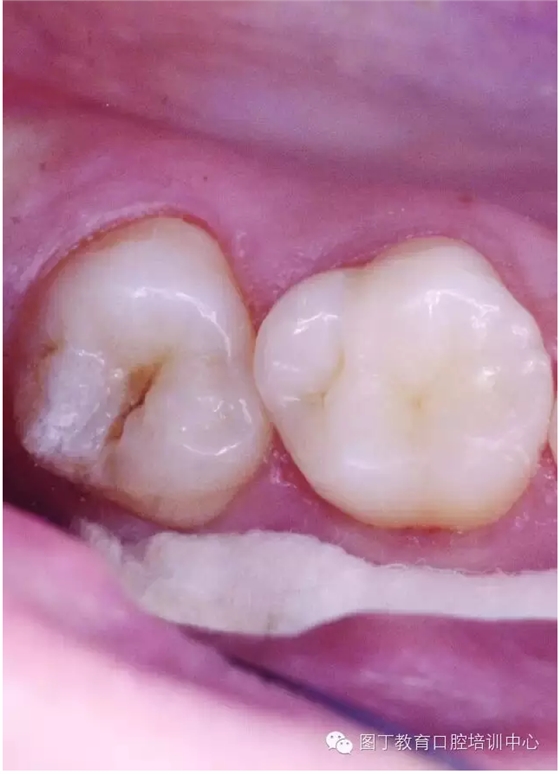

窩溝封閉前后

窩溝封閉前

窩溝封閉后

易患齲的深窩溝和早起齲損

高質(zhì)量的封閉,對(duì)于任何年齡的都有益